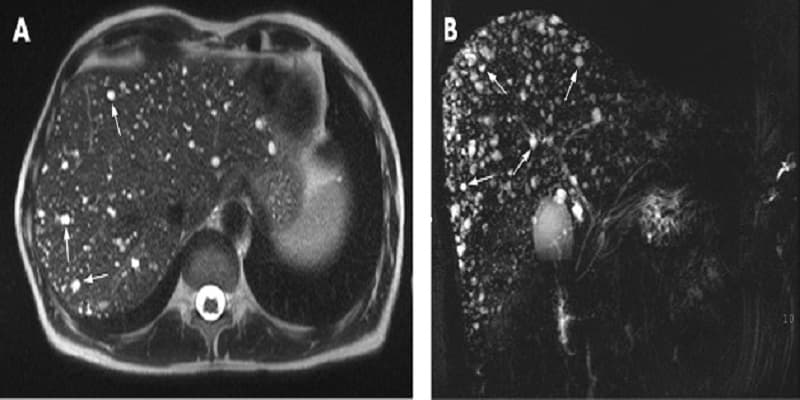

Siêu âm gan là phương pháp phổ biến giúp phát hiện các thay đổi về kích thước, mật độ và cấu trúc gan. Bên cạnh đó, các kỹ thuật như siêu âm đàn hồi, chụp CT và MRI gan cũng được sử dụng để xác định mức độ xơ hóa. Nội soi tiêu hóa có thể được thực hiện nếu nghi ngờ tình trạng giãn tĩnh mạch thực quản hoặc chảy máu trong. Ngoài ra, nội soi mật tụy ngược dòng giúp đánh giá các bất thường liên quan đến đường mật.